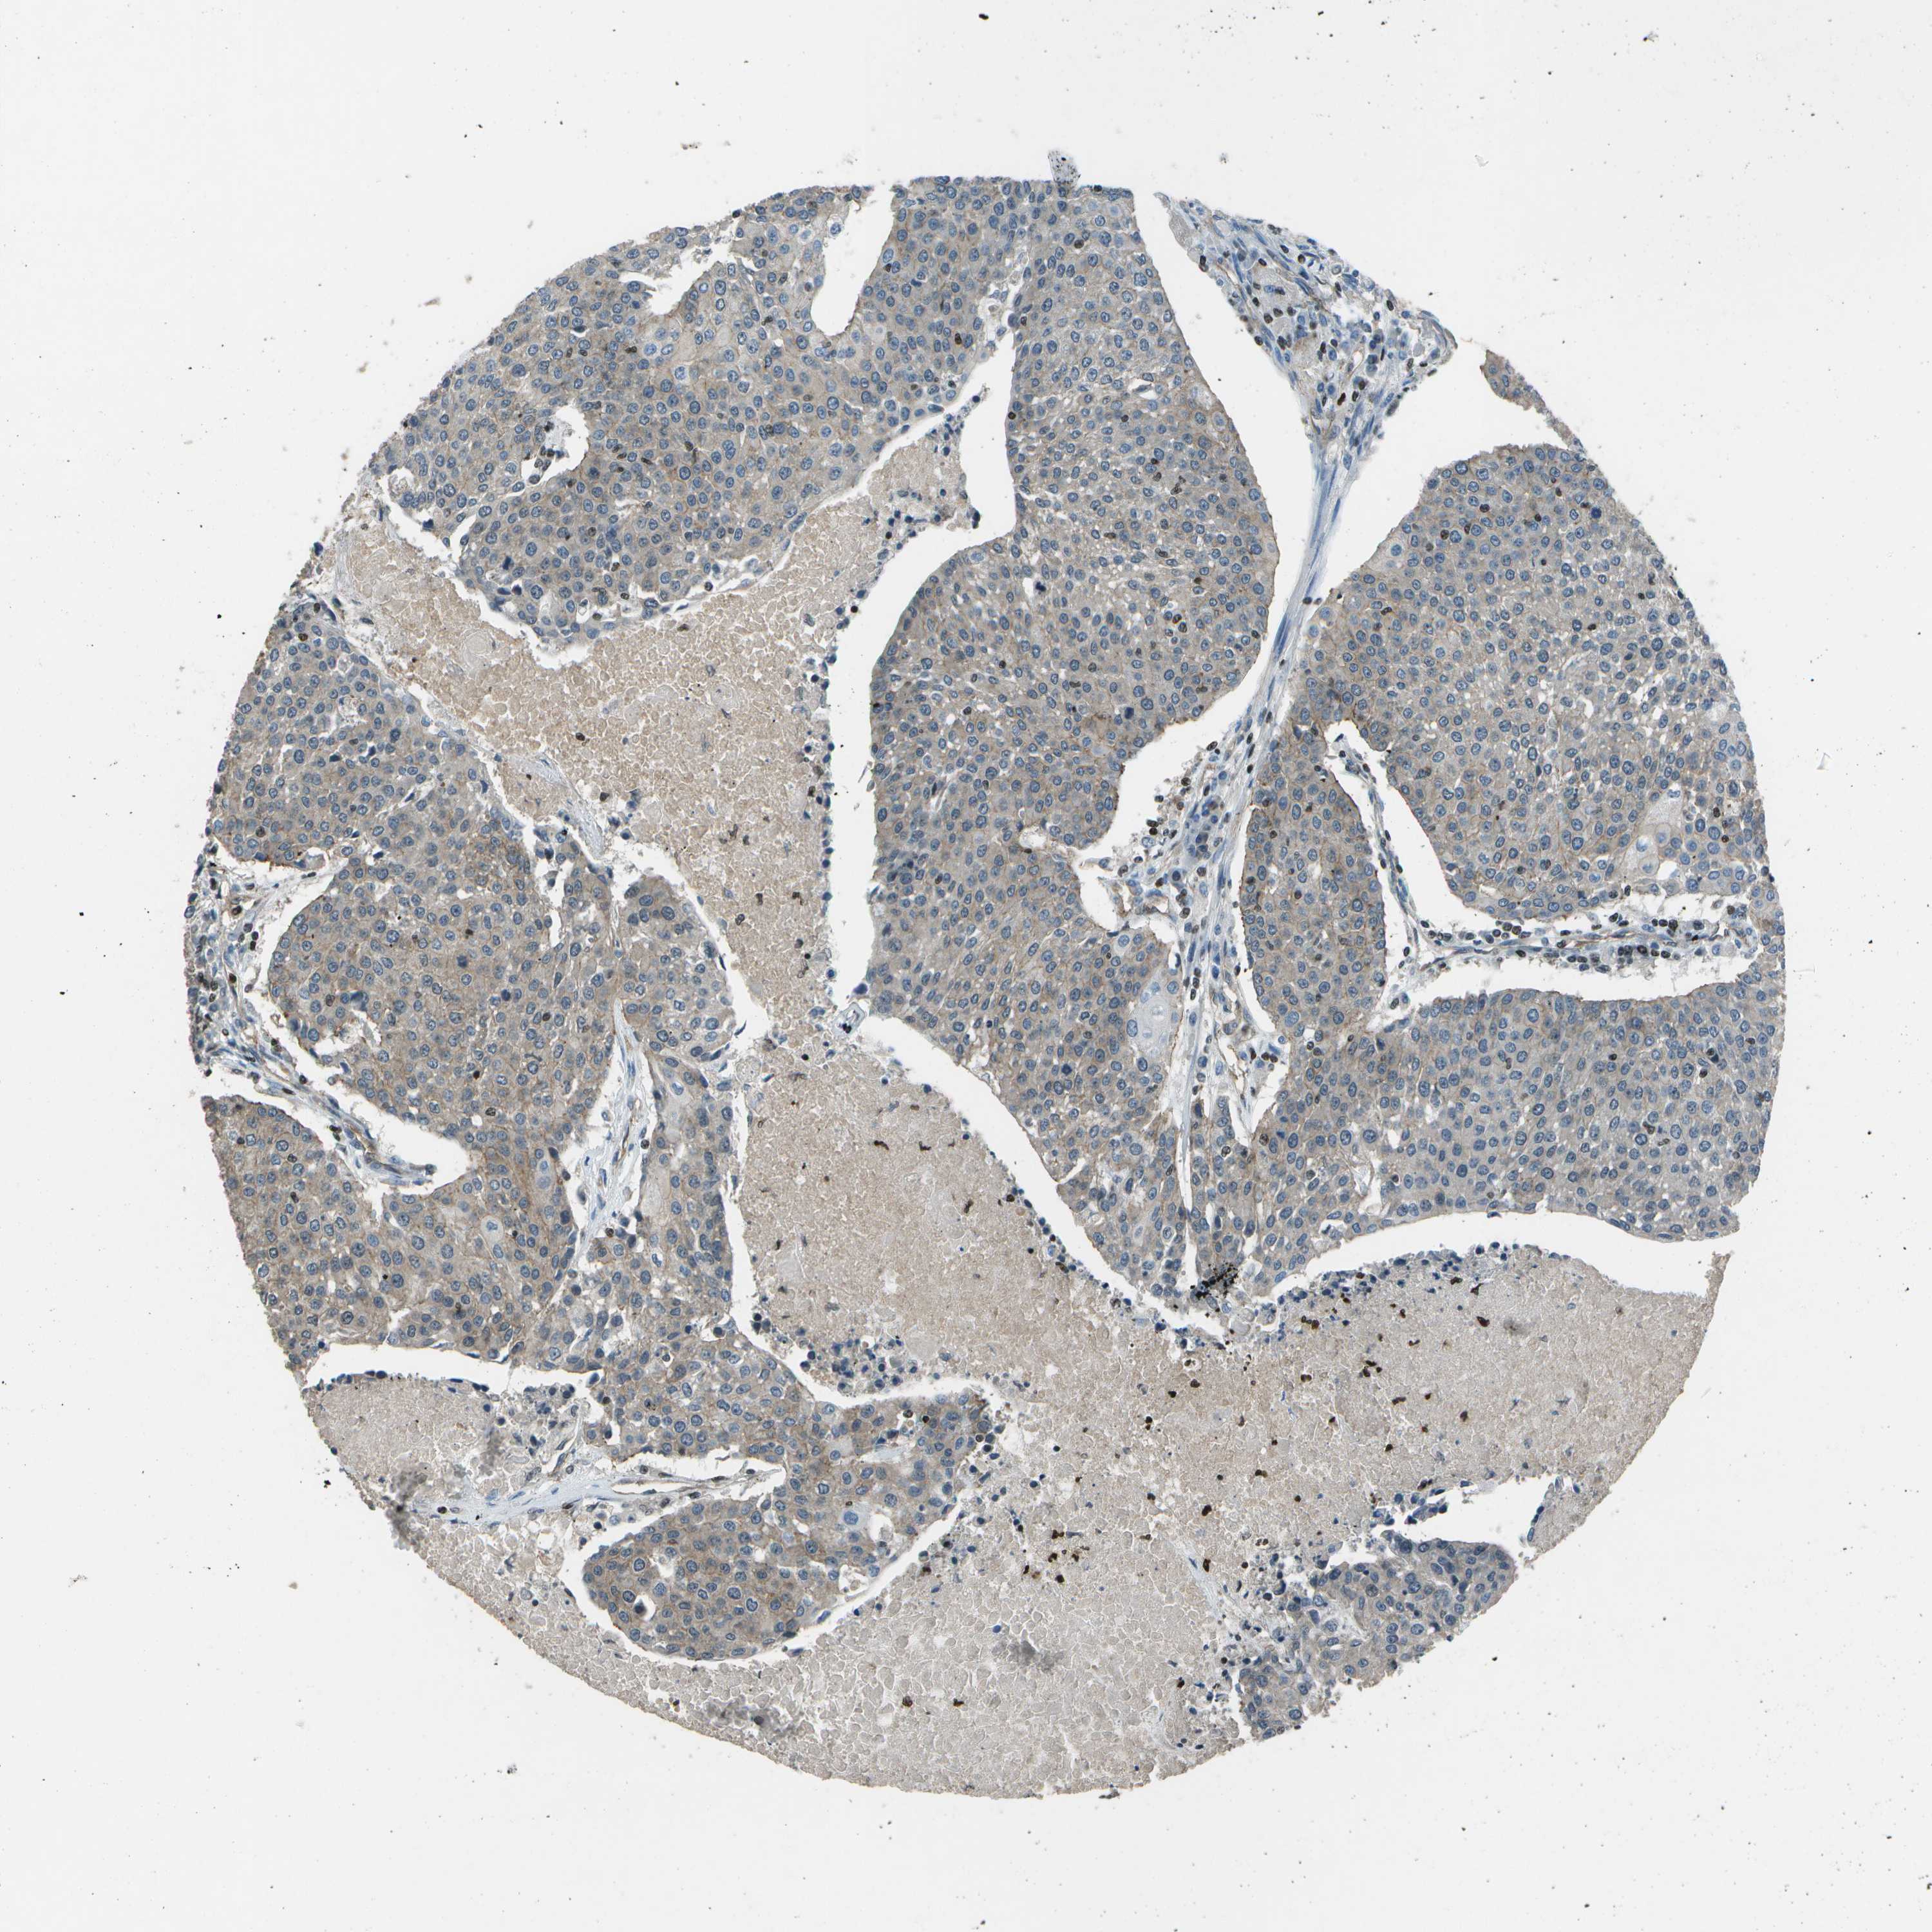

UROTHELIAL CANCER - Protein expressioni

A mouse-over function shows sample information and annotation data. Click on an image to view it in a full screen mode. Samples can be filtered based on level of antibody staining by selecting one or several of the following categories: high, medium, low and not detected. The assay and annotation is described here.

Antibody stainingi

Antibody staining in the annotated cell types in the current human tissue is reported as not detected, low, medium, or high, based on conventional immunohistochemistry profiling in selected tissues. This score is based on the combination of the staining intensity and fraction of stained cells.

Each image is clickable and will lead to virtual microscopy that enables deeper exploration of all samples and also displays staining intensity scores, fraction scores and subcellular localization as well as patient and tissue information for each sample.

Antibody HPA017010

Antibody CAB072838

Staining

High

Medium

Low

Not detected

Intensity

Strong

Moderate

Weak

Negative

Quantity

>75%

75%-25%

<25%

None

Location

Nuclear

Cytoplasmic/membranous

Cytoplasmic/membranous,nuclear

Urothelial carcinoma, NOS

Urothelial carcinoma, High grade